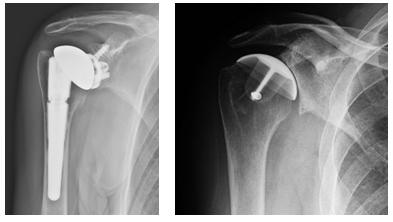

Negli ultimi decenni sono state messe a punto delle componenti omerali più conservative e meno invasive. Questo significa togliere meno osso e riempire un tratto più breve dell’omero. Queste protesi più rispettose della struttura ossea sono le “protesi di rivestimento” e le “protesi emicefaliche” (ovvero “di metà testa”). Trovano indicazione quando il danno alla superficie articolare non è troppo esteso, l’omero prossimale non è deformato e la consistenza dell’osso è soddisfacente. Pertanto si impiantano in una fascia di età più giovanile rispetto alla media delle protesi.

Una protesi di rivestimento è una sorta di calotta metallica che va appunto a rivestire la testa omerale dopo averla preparata con frese sferiche.

Una protesi emicefalica si mette invece dopo avere resecato uno strato sottile della testa omerale ed è dotata di un breve fittone che non arriva a penetrare nel canale midollare.

Queste protesi sono state ideate con lo scopo di sacrificare meno osso, quindi conservare uno “stock” osseo più abbondante per eventuali futuri reinterventi, ma si possono impiantare solo in una minoranza dei casi. Anche i materiali delle protesi stesse hanno subito una forte innovazione negli ultimi anni, con lo sviluppo di rivestimenti più biocompatibili e rispettosi del tessuto ospite, sia osseo che cartilagineo: gli steli sono maggiormente integrati da parte del tessuto osseo ospite, che letteralmente si “aggrappa” in maniera naturale alla componente protesica stabilizzandola permettendoci di non utilizzare il cemento per la fissazione, e le superfici di scorrimento sono più simili alla cartilagine articolare e quindi delicate su quest’ultima, come ad esempio il pirocarbonio.

Componente glenoidea – Quando è degenerata anche la superficie articolare della scapola (la glena o glenoide), ai tre tipi di protesi omerali già visti – anatomica, di rivestimento, emicefalica – si accoppia una componente scapolare con superficie concava, che può essere composta da una base metallica (il “metal back”) su cui si incastra una sorta di scudo in polietilene (fig. 9 e 13); oppure può essere tutta in polietilene (fig. 12).